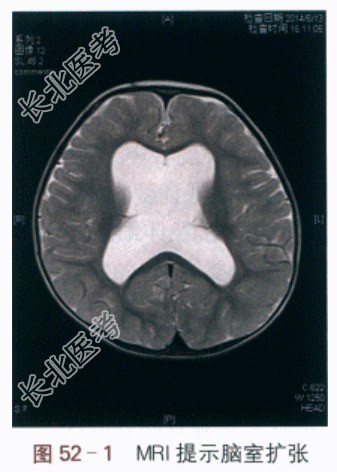

1.现病史患儿,男性,1岁3月。因“头围增大半年”入院。患儿产前检查无异常,1周岁后发现仍不能行走,可独自站立,近半年来发现头围增大,行MRI检查发现“脑积水、导水管狭窄,脑实质未见异常信号”(见图52-1)。为进一步治疗于我院就诊,门诊拟诊“脑积水”收入院。

2.既往史G₁P₁,产前检查无异常。父母体健,预防接种史正常。家族中无类似病例。3.体格检查神情,精神反应正常,头围增大,48cm,囟门未闭,约2cm×2cm,可独自站立,不能行走,语言发育落后,仅能发单个音节;胸廓平坦,三凹征阴性,听诊双肺呼吸音清,未闻及啰音,心音有力,律齐,未闻明显杂音;腹平软,肝脾未及;四肢无畸形,肌力及肌张力无异常,未见明显脊柱侧弯;肛门牛殖器未见异常。4.实验室及影像学检查血常规:RBC4.5×10¹²/L,PLT212×10⁹/L,WBC9.9×10⁹/L,Hb117.0g/L。肝肾功能检查:DB1.0μmol/L,TB2.8μmol/L,ALT8.0IU/L,AST23.0IU/L,ALB44.4g/L,Cr21.0μmol/L,BUN4.2mmol/L。凝血功能:APTT33.1s.FDP2.28g/L,INR1.24,PT14.6s,PTA113.0%,TT18.5s。MRI:双侧脑室扩张伴透明隔缺如。